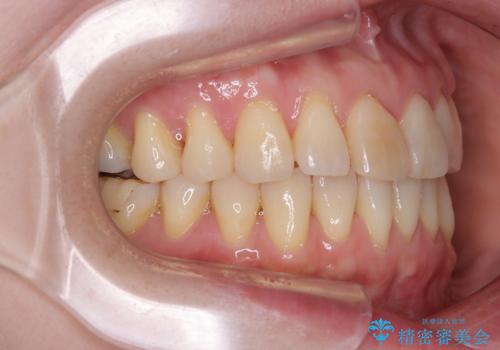

前歯のデコボコをインビザライン・モデレートで矯正治療

- 上下前歯のデコボコを気にして来院された患者様です。

安価なインビザラインパッケージを用いての治療を希望されており、デコボコの程度が中等度であったため、インビザライン・モデレートを用いて矯正治療を行うこととしました。

インビザライン・モデレートは、製作できるアライナーの枚数に制限があるため、移動可能な量に限りがあるものの、インビザライン・ライトよりも枚数が多いため、幅広い症例に対応可能です。